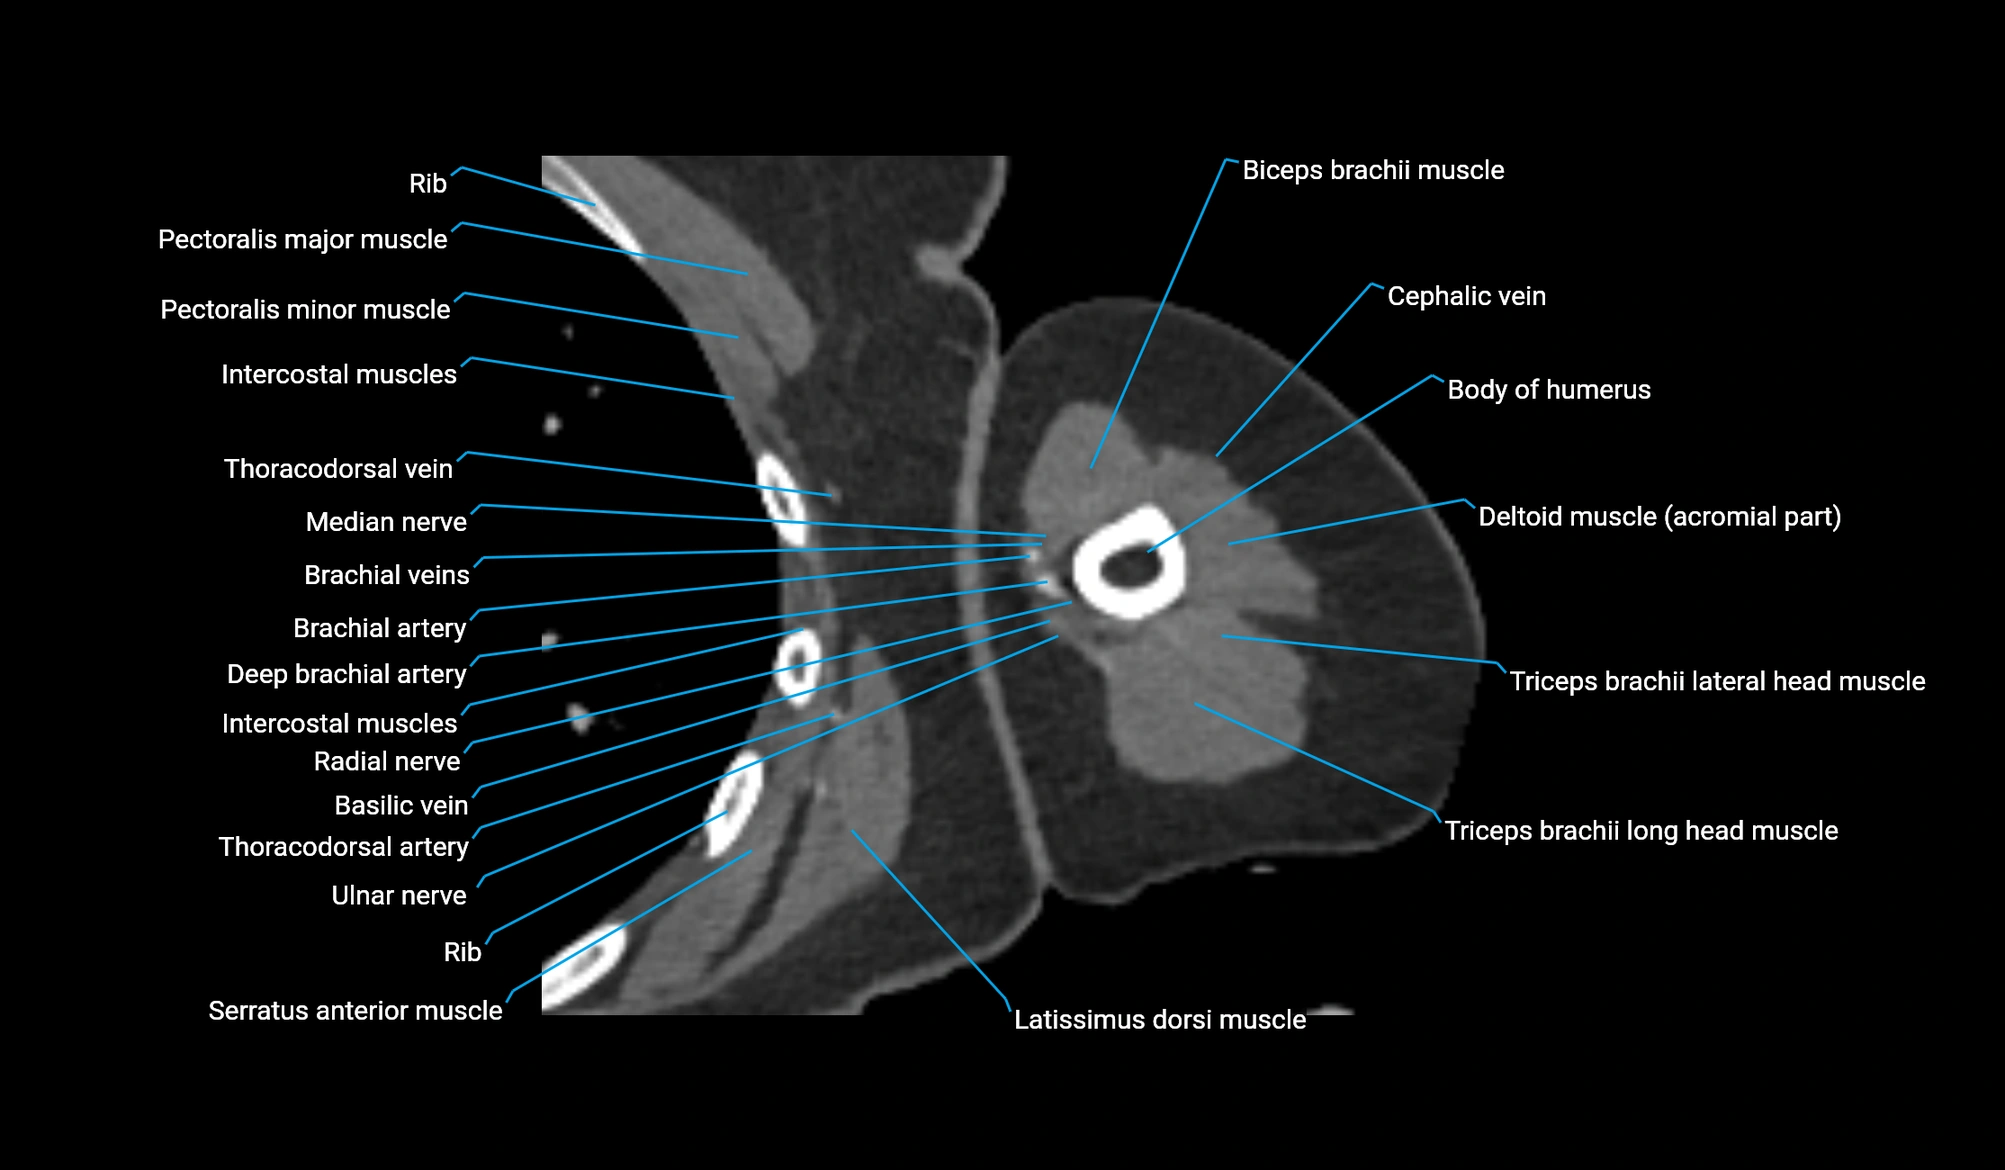

- Body of humerus

- Brachial artery

- Brachialis muscle

- Cephalic vein

- Deep brachial artery

- Lateral head of triceps brachii muscle

- Long head of triceps brachii muscle

- Median nerve

- Pectoralis major muscle

- Pectoralis minor muscle

- Radial nerve

- Thoracodorsal artery

- Ulnar nerve

- Basilic vein

- Biceps brachii muscle